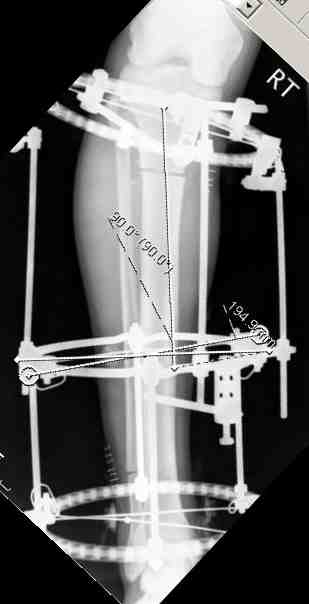

Представлены фотографии и рентгенограммы 21летней девушки, страдающей от bilateral leg malalignment syndrome. The next figure shows pictures and x-rays of 21 y.o. female with bilateral leg malalignment syndrome

Перед лечением. Before treatment

После деротации левого бедра и голени. After derotation osteotomy of lt femur and tibia

Результат The final result after derotation osteotomies of rt femur and tibia.

В верхнем ряду показаны рентгенограммы до, после коррекции и после снятия аппарата Илизарова. On the upper row the X-rays of lt leg before correction, after correction and after apparatus removal have been showed.

В нижнем ряду представлены два снимка после коррекции деформации правой голени. Видно, что качество коррекции не зависит от квалификационного наложения аппарата Илизарова, что было специально произведено для проверки работы программы. Lower two X-rays – rt leg after deformity correction. As you can see the quality of correction does not depend of placement of Ilizarov Apparatus